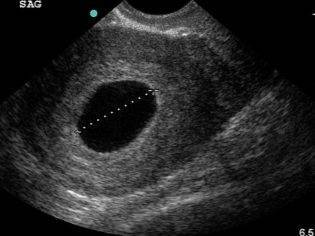

Для измерения используется специальная методика. Диагност УЗИ так прокладывает прямую визуальную линию через плодное яйцо, которое видит на мониторе, чтобы концы отрезка располагались на противоположных друг другу точках внутренней оболочки плодного мешка. Этот размер носит название СВД – средний внутренний диаметр.

Этот размер определяется самым первым. Затем к нему добавляется копчико-теменной размер самого зародыша. Немаловажным также считается размер желточного мешочка.

Нормы роста можно увидеть в таблице.

Плодное яйцо на 6 неделе и до этого срока беременности имеет овальную форму. И на ультразвуковом исследовании обычно производится оценивание внутреннего его диаметра – СВД плодного яйца. Так как размер плодного яйца 7 недель или на другом сроке беременности является величиной вариабельной, то есть погрешность в выявлении срока беременности по этому фетометрическому показателю.

В среднем подобная погрешность составляет 10 дней. Срок беременности обычно определяется не только по данному показателю, но также используется значения копчико-теменного размера плода и прочие показатели, которые также очень важны